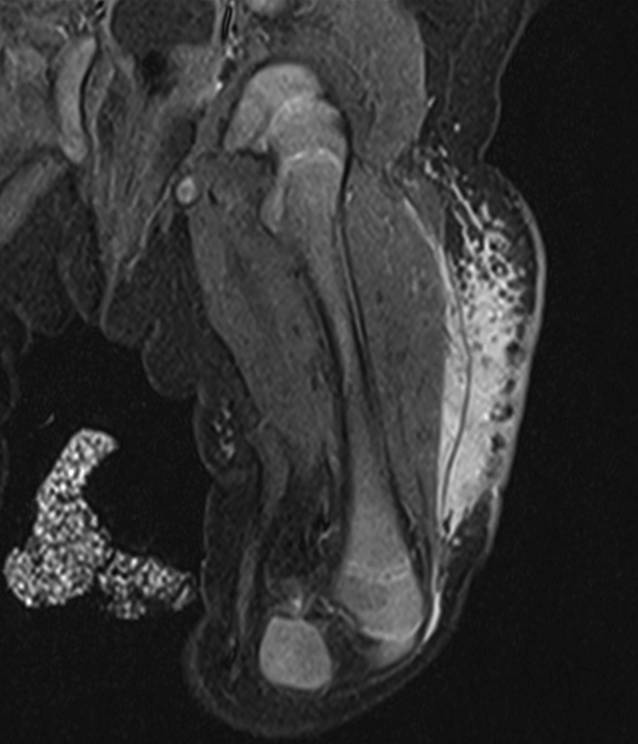

Abb. 4

Patientin 2. Im koronalen T2-Magnetresonanztomogramm findet sich eine gemischte mikro-/makrozystische Läsion mit Punctum maximum am Hals rechts, die auch auf die Gegenseite reicht

Fallbericht 2

Bei dieser Patientin wurde bereits in einem pränatalen MRT eine ausgedehnte, überwiegend makrozystische Veränderung mit Punctum maximum inframandibulär beidseits, die bis an den Meatus acusticus externus, die Schädelbasis und die Infratemporalregion heranreichte, beschrieben (Tab. 1). Es fanden sich Ausläufer bis in den Zungengrund sowie den Oro- und Hypopharynx. Ab dem 2. Lebenstag erhielt die Patientin Sirolimus. Die erste postpartale MRT erfolgte am 5. Lebenstag und zeigte eine gemischte groß- und kleinzystische lymphatische Malformation (Abb. 4). Zur Sicherung der Atemwege erfolgt unmittelbar postpartal die gesetzte Intubation und am 16. Lebenstag die Anlage eines Tracheostomas sowie die erstmalige Sklerosierung der großzystischen Areale durch Instillation von OK 432. Die Betreuung erfolgte interdisziplinär durch Kinderchirurgie, pädiatrische Hämato-/onkologie und pädiatrische Pulmonologie. Weitere OK-432-Instillationen wurden im 2. und 5. Lebensmonat durchgeführt. Sirolimus wurde insgesamt ausgezeichnet toleriert. Die Dosen wurden nach Körpergewicht und Serumspiegel entsprechend adaptiert und lagen zwischen 0,035 und 0,0625 mg/kg und Tag. Es traten zwar mehrfach fieberhafte respiratorische Infekte auf, die jedoch nicht über das bei nicht immunsupprimierten Patienten in diesem Alter übliche Ausmaß hinausgingen. Es kam klinisch und radiologisch zu einer deutlichen Größenabnahme der lymphatischen Malformation, die auch in der im Alter von 6 Monaten durchgeführten MRT bestätigt wurde (Abb. 5).